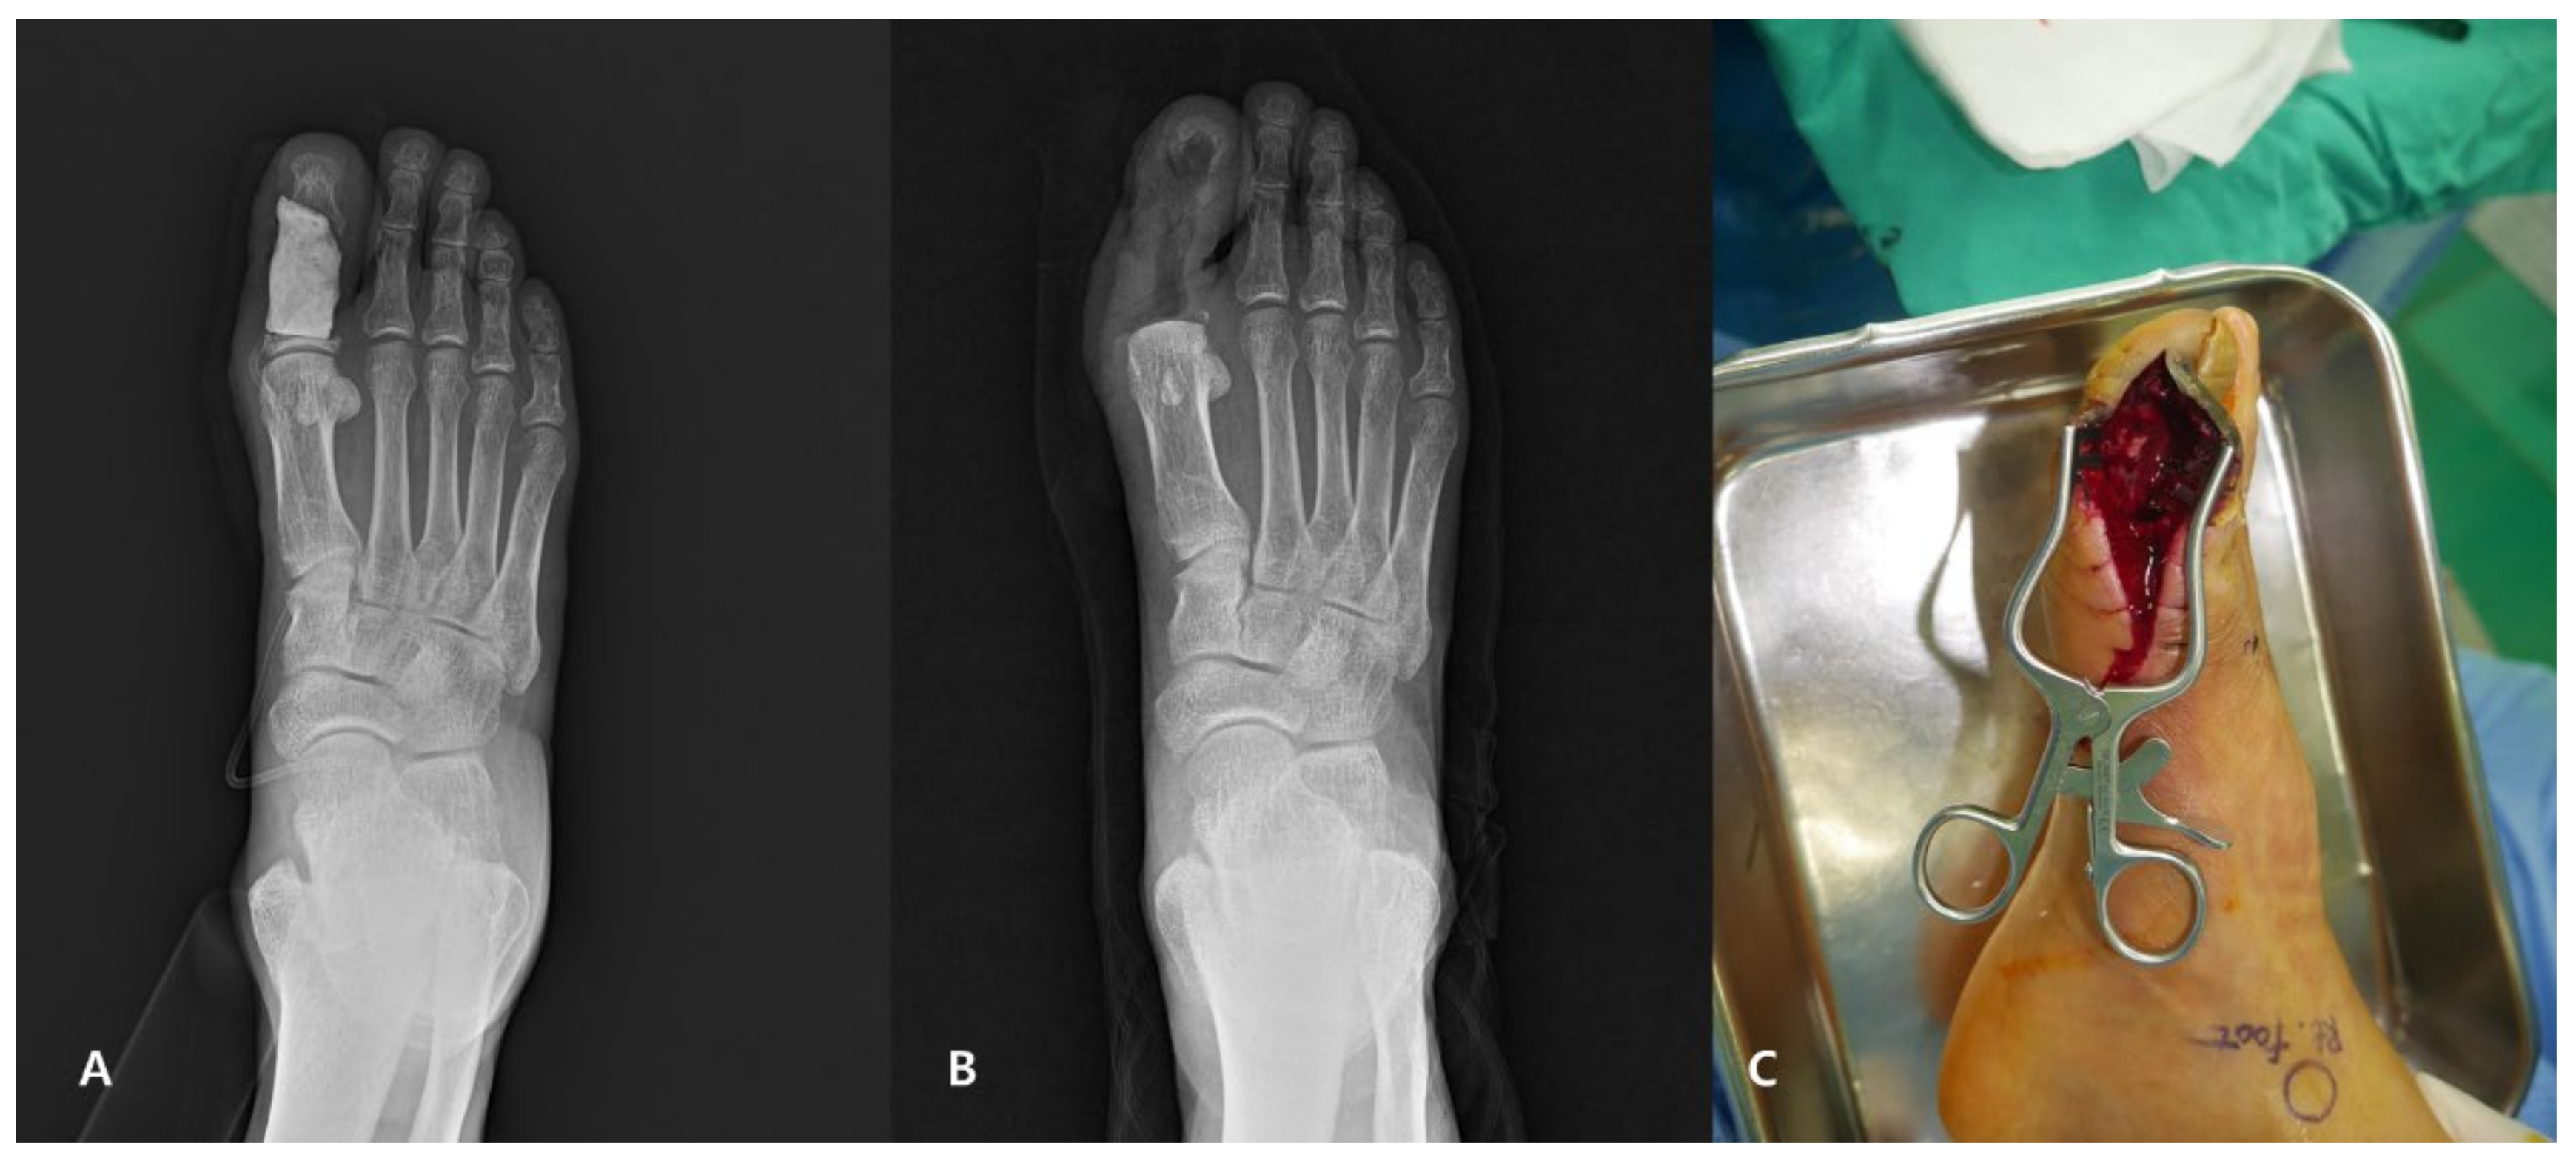

2.3. Surgical Technique